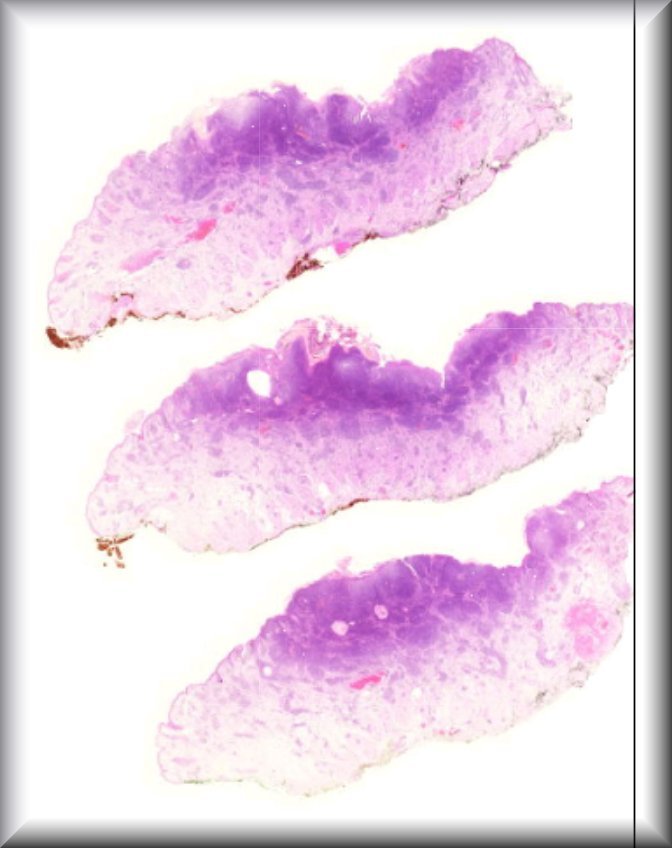

Sandra Lassalle (Guest): A 15 year old woman presenting with a left eye conjunctival pigmented lesion. The lesion has recently changed. Removal of the lesion has been approved. There is no particular clinical history. |